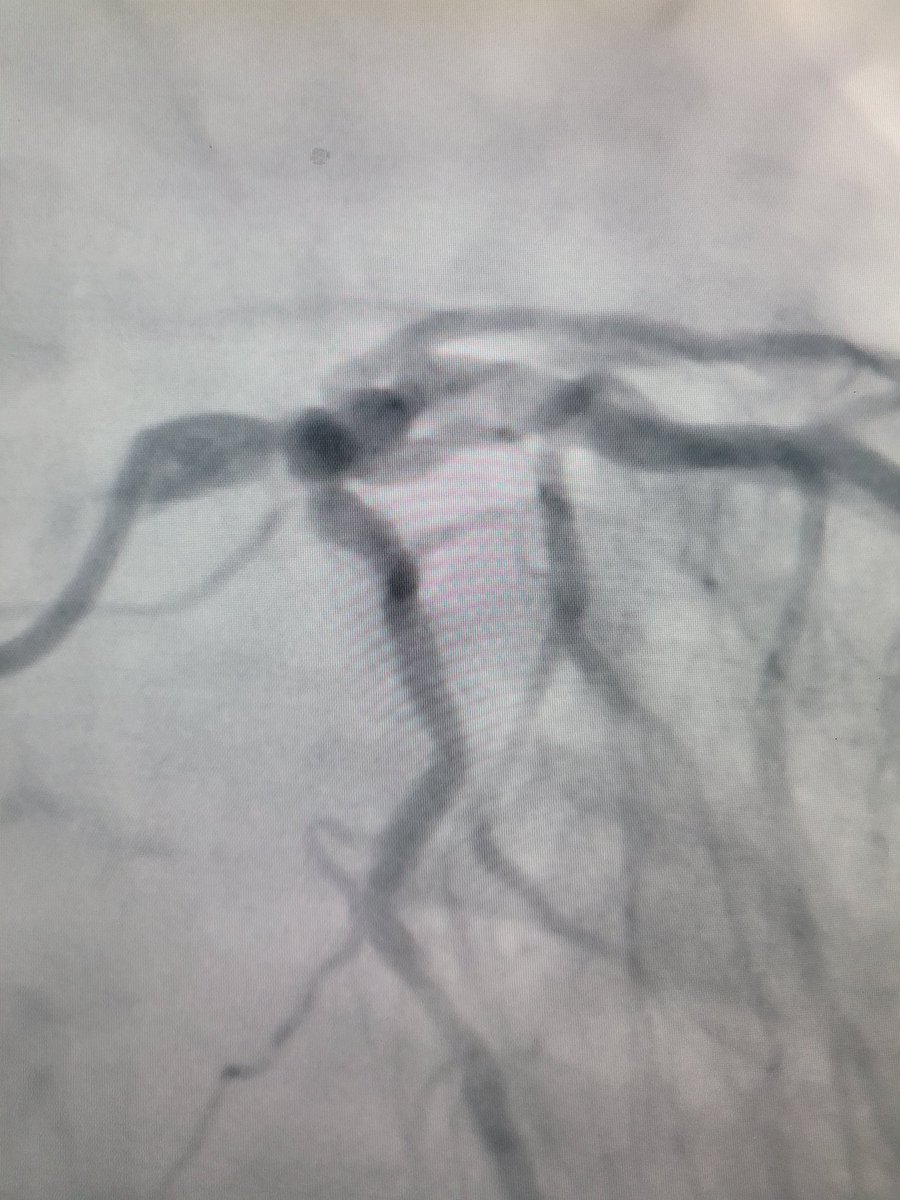

🙍🏻 ♂️ Enfermedad arterial coronaria multivasos. 3 lesiones en bifurcación incluyendo el tronco de la coronaria izquierda #leftmain. Se realiza intervención coronaria percutánea con una revascularización completa. #interventionalcardiology #cathlab #cardiologia #PCI #EACMV #IHD